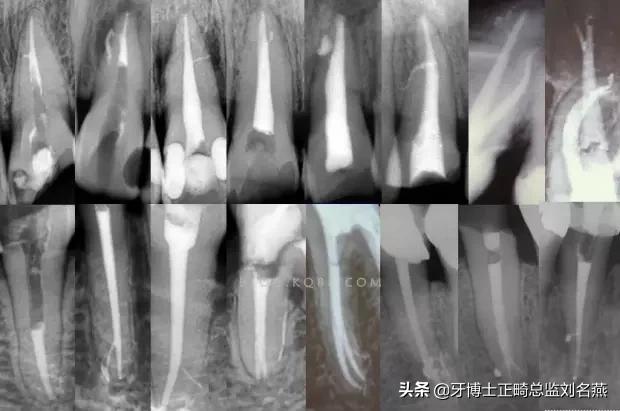

2、相信有更多的根管存在

相信根管的数目比我们想象的多,根管系统的复杂程度比我们想象的见到的要更复杂,我们只有用尽所有努力和办法才可能达到预期目标。

对于上颌第一磨牙的MB2来说过去是偶尔有,现在是偶尔没有,各种文献报道的比例也不一致,在离体牙中几乎还没有见到没有的,临床中也是一样。对于寻找的方法来说,我觉得相信有才是最重要的,首先相信一定有就会想各种办法,找到的几率就会更多。如果有条件在显微镜和超声的配合下效率会更高。

5、预备到多少号结束

根管预备理想的情况应该预备到多大锥度,多少号,预备后根管空间是金字塔还是埃菲尔铁塔。专家经过离体牙根尖切片研究发现根尖狭窄部远比想象的要大,如果根管预备太小就会残留感染物,根管的部分空间就不会预备到,残留的感染物就会造成治疗效果达不到预期目标。只有做到了充分的预备,尽可能地多冲洗才会有好的结果。

根管治疗要做到看清楚,去干净,充恰满,封严密,就会达到期望的结果。2200年前的病例只充填了冠1/3可以理解、可以接受;2200年后的今天我们有先进的设备和材料,就要充填出大锥度高密度的完美结果。理念决定技术,标准决定技术的提高和进步。